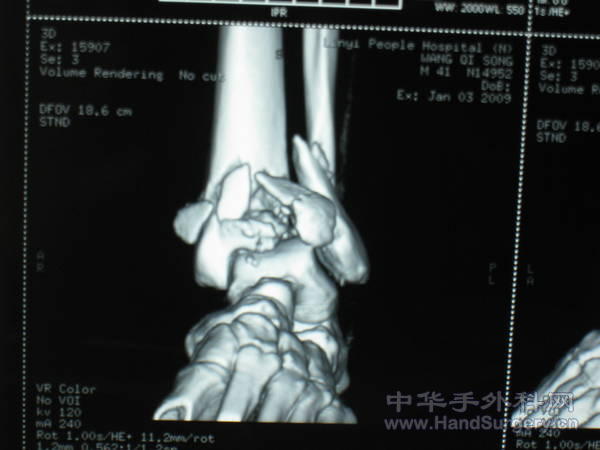

pilon骨折一例-手足外科魏宝富主任作品

这种骨折为从高坠落高能量致的损伤,损伤都较重,对重的有的主张一期行关节融合,如轻的可以行复位内固定,一般都要行植骨。

pilon骨折在哪做都是高难度手术,骨性支架的建立应该最重要,皮肤缺损对手足外科大夫来讲已经不是什么难题 ,希望看到踝关节关节面的x线或ct。

魏主任:你的手术做的很好,但是不知关节面是如何处理的,植骨了吗?是急症做的还是消肿以后做的?切口愈合如何?还有外侧的关节面好像没有处理?

对于此类骨折,手术最关键所在应该是先恢复腓骨解剖位置,其余骨折块做起来较容易些。另外需要注意植骨支撑,再者注意下胫腓关系一定要稳定!不要轻易去做融合!个人理解